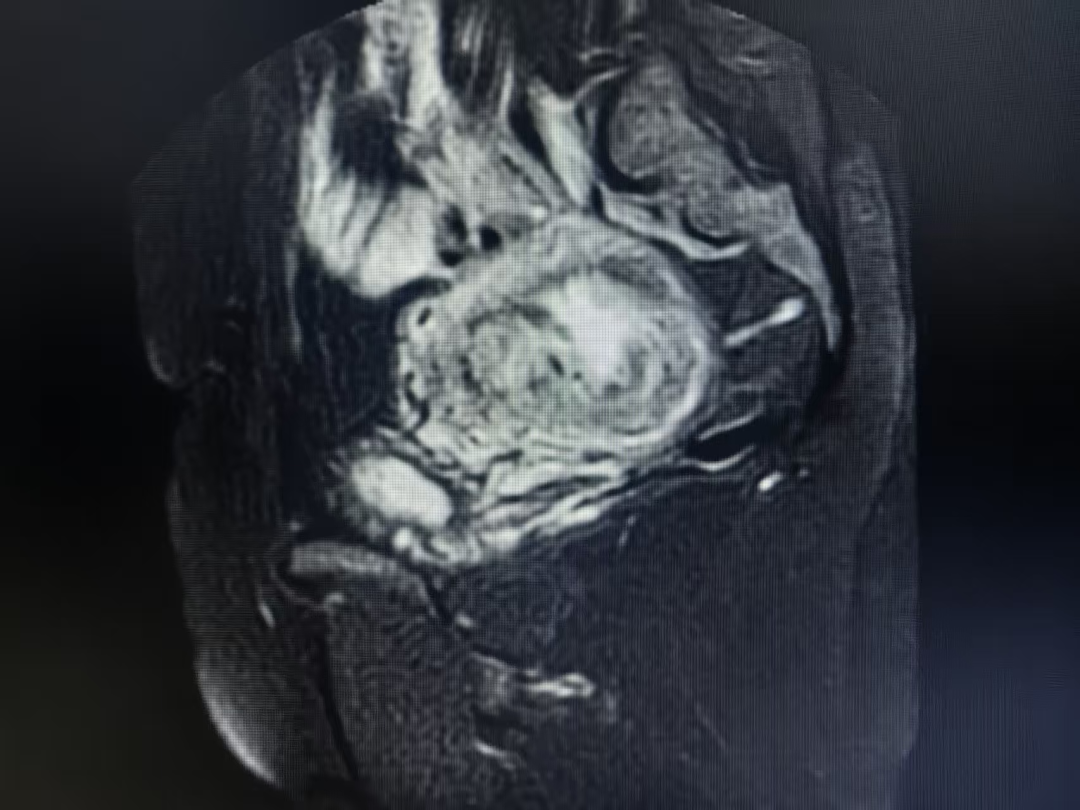

专家团队全面评估患者病情、结合患者需求,精准研判术中大出血、脏器损伤等高危风险,反复推演后制定“术前子宫动脉介入栓塞+双侧输尿管双J管置入术+子宫次全切除术”个体化救治方案。

手术中,各学科紧密配合、精准操作,妇科、泌尿外科、介入、麻醉团队密切配合,凭借丰富的临床经验和娴熟的手术技巧,全程操作精准、止血彻底。在多学科团队的通力协作下,手术顺利完成,患者术中出血量得到有效控制,生命体征平稳。术后在医护人员的精心照料下,恢复状况良好,各项指标逐渐趋于正常,不久后便顺利康复出院。